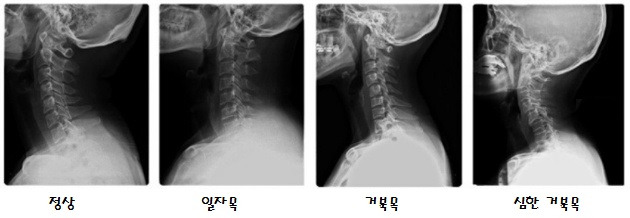

목뼈가 '1'자로 되어 '일자목', 가만히 있어도 머리가 앞으로 구부정하게 굽어지는 자세를 보고 마치 거북이의 목과 유사하다고 하여 '거북목' 이라고 불리며 고개를 들 수 없을 정도의 통증, 어깨를 손으로 부여잡고 있지 않으면 아무것도 할 수 없을 정도의 고통이 잇따르기도 한다.

증상 단계는 총 세 단계로 나눠볼 수 있다. 첫째로 가장 정상인 C자형 목, 둘째로 일자목, 셋째로 거북목이다. 증상이 심한 거북목은 역 C자형 목이 된다.